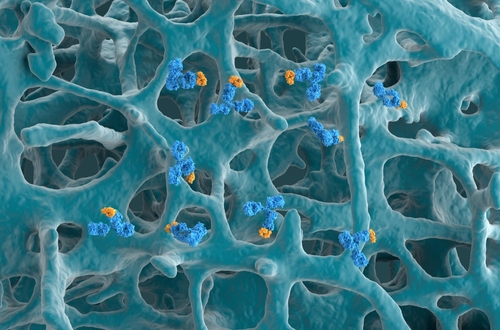

Dr. Castro and colleagues conducted a post hoc analysis of phase 3 NAVIGATOR study data to assess the effectiveness of tezepelumab, a human monoclonal antibody that blocks thymic stromal lymphopoietin, in patients who were former smokers and patients who were never smokers.